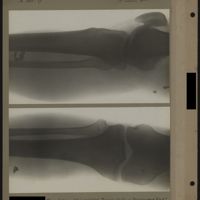

0014 - Page 10 - [Radiographies de l'articulation du genou, du tibia et de la fibula]0014 - Page 10 - [Radiographies de l'articulation du genou, du tibia et de la fibula]